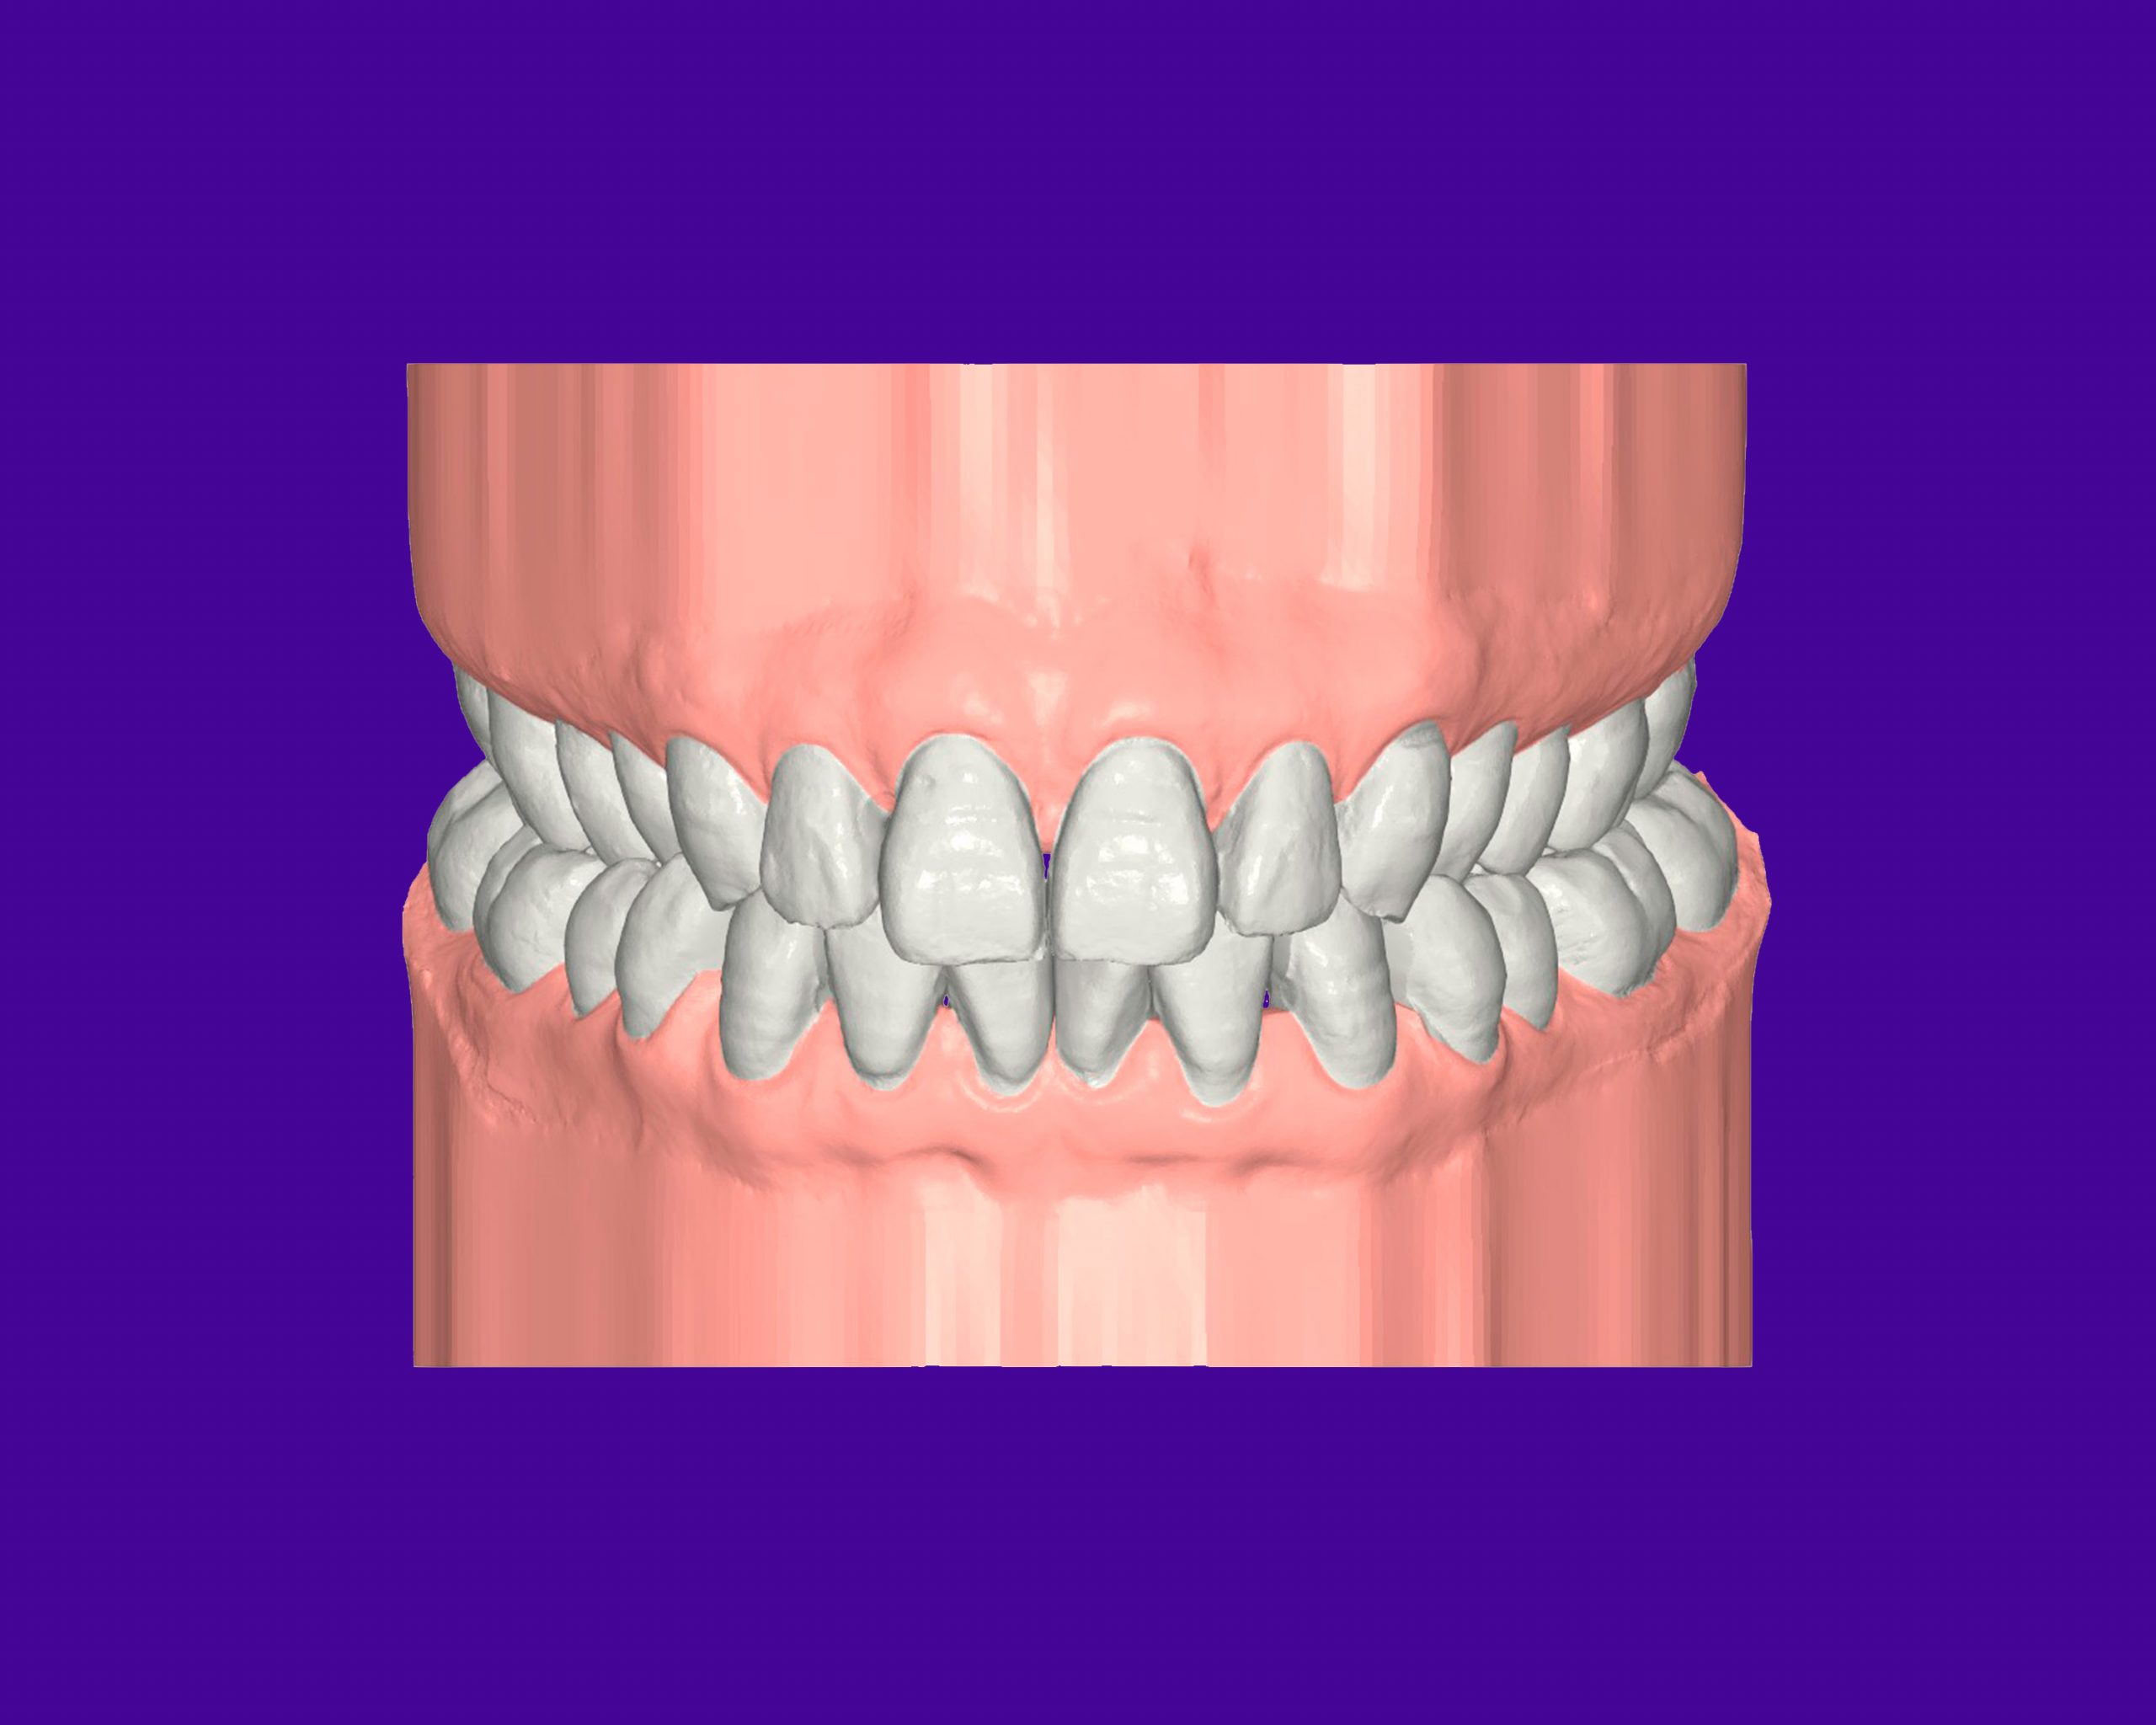

FULL

37 Semanas de tratamiento